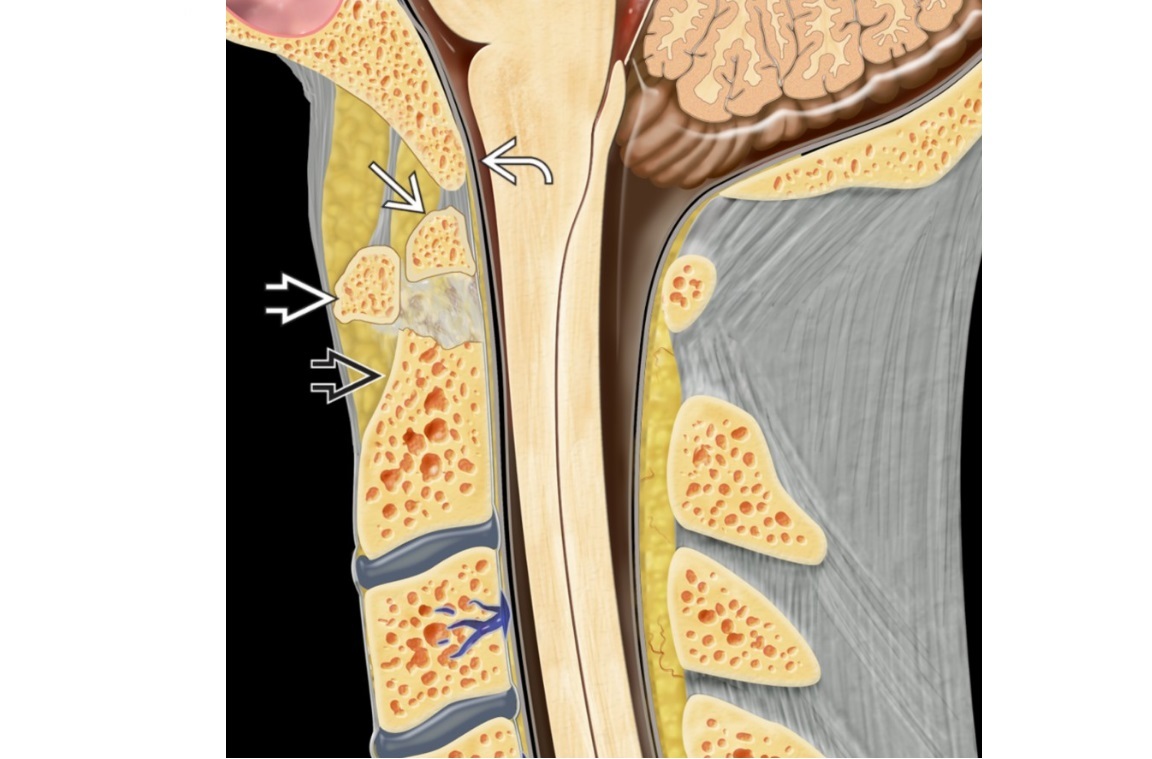

Intramedullay, intradural and extradural spinal lesions

see picture